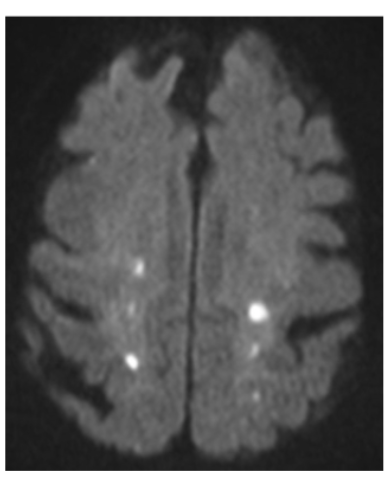

Q

What type of stroke is shown on the provided DWI image?

A

punctate

small, round infarcts cortically & in both hemispheres

22

The punctate stroke shown in the provide image is suggestive of what etiological cause?

cardioembolic etiology